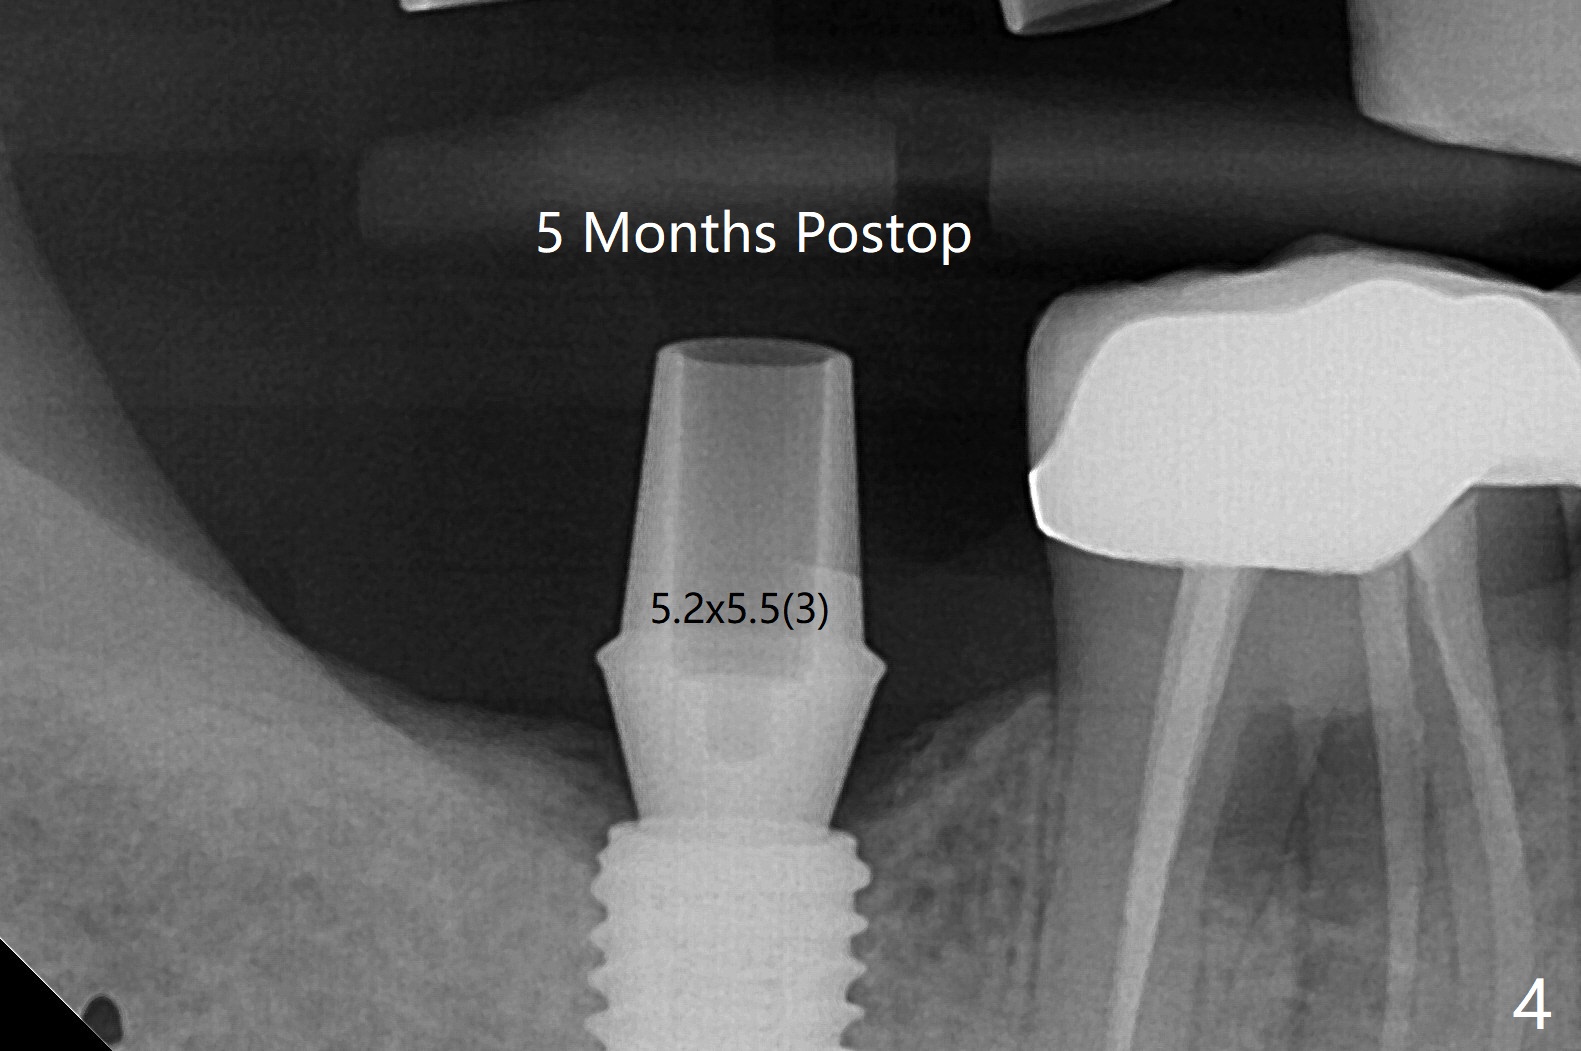

Incision is made at #2 and 3 because of bone graft palatal to #2 after implantation and 6-month-old guides (coronavirus pandemic). The implant at #3 is first placed with precision; there is no hesitation with that at #2. The palatal bone defect is confirmed. With autogenous bone placed around the implant/abutments covered by pieces of collagen membrane, the wound is closed with 4/0 Chromic gut suture. Since the keratinized tissue is wide at #31, osteotomy starts with a tissue punch. The implant placement level is noted accurate clinically and radiographically (Fig.1,2). The 3 implants have the same size (5x10 mm). All of the sites use 6.0 mm bone profile drill before healing abutment insertion. The surgery turns out to be smooth and streamlined. Abutments are placed 5 months postop (Fig.3,4). The upper crowns are redo twice because of light occlusion and proximal contact and finally are cemented 9 months postop with torque at 20 Ncm.